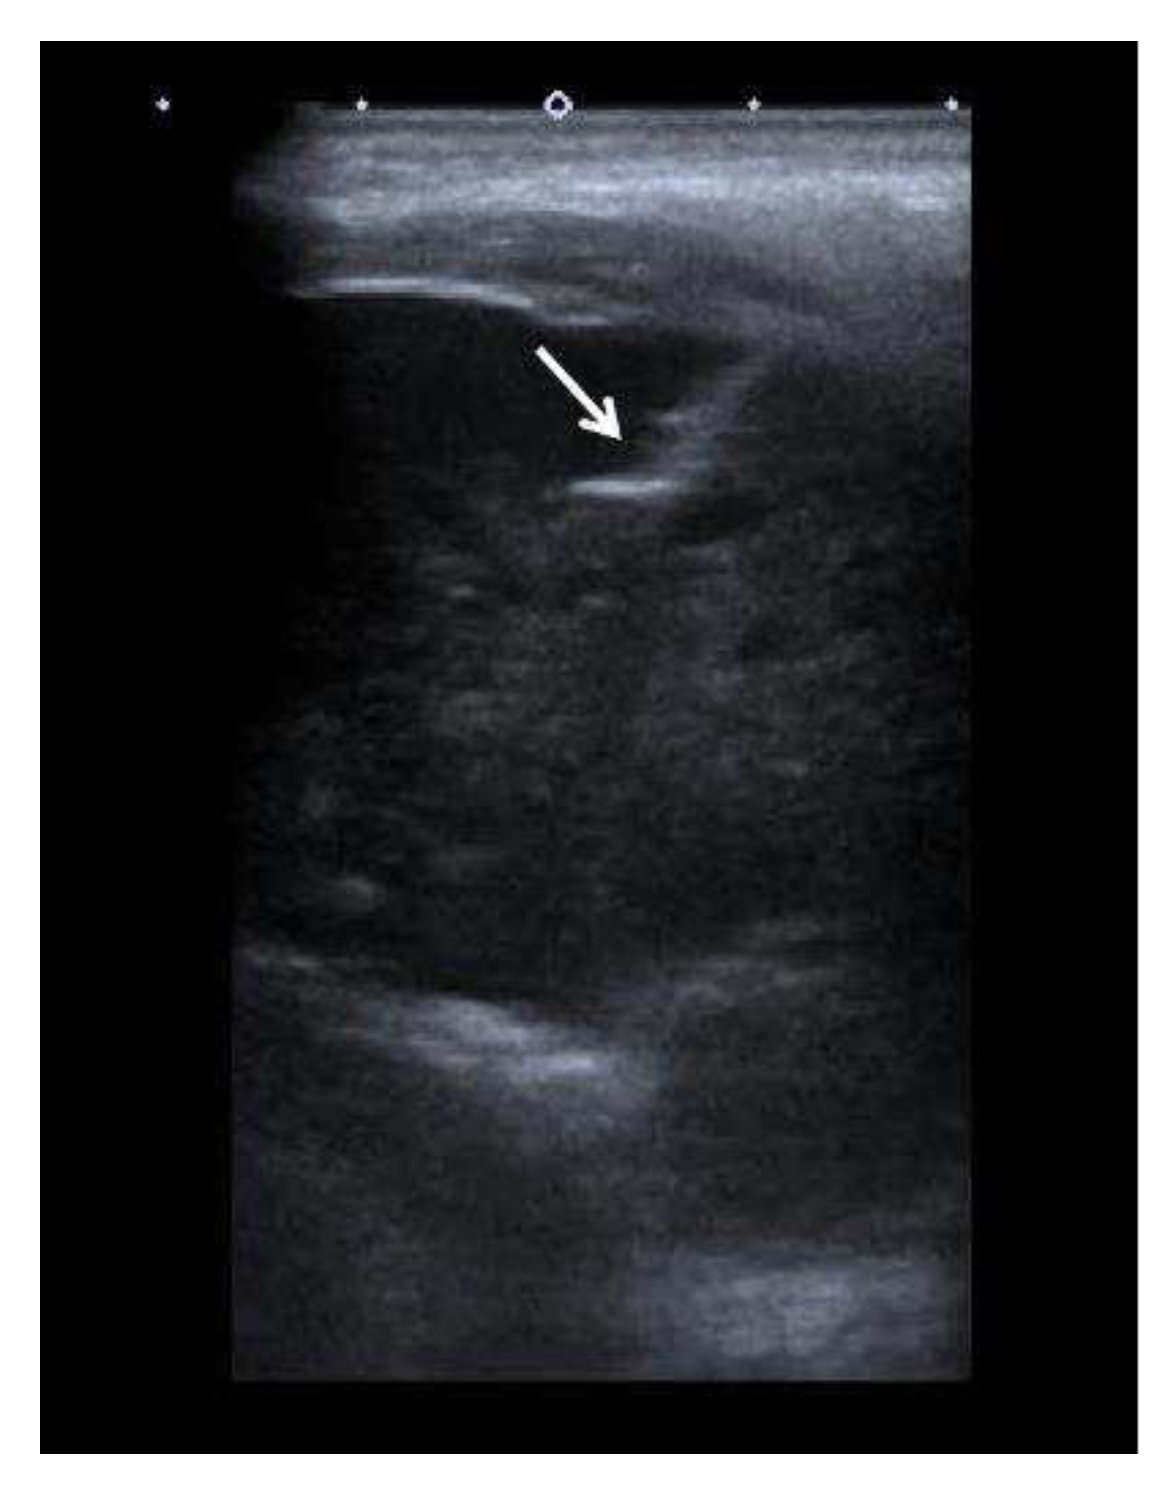

The patient was referred to the Department of Interventional Radiology in consideration of a percutaneous biopsy of the mass. The core biopsy was performed (Figure 3), and PH findings indicated a metastatic carcinoma in the left mandible, completely consistent with previously diagnosed trabecular type of hepatocellular carcinoma (Figure 4). There were no other sites of disease dissemination upon an endocranial, neck, chest, abdominal and pelvic CT performed shortly after. The maxillofacial oncological team concluded that due to the prolonged recovery from COVID 19 disease, as well as due to the accelerated disease progression and poor prognosis of the patients with extrahepatic disease, the surgical treatment of mandible lesion was not indicated and the treatment was continued with symptomatic and palliative treatment. Ten months later the patient died due to hepatic decompensation and local spread of the metastatic disease. However, there were no clinical or radiological signs of recurrent disease in the liver.

Typically, the radiologic presentation of HCC bone metastasis is an osteolytic soft-tissue mass, commonly hypervascular as the primary HCC itself [16]. In that respect it is understandable why the lesion itself is prone to bleeding [15,17]. Due to the afore mentioned bone metastasis of HCC characteristics, special care needs to be taken while performing biopsy, therefore, percutaneous core biopsy or fine needle aspiration (FNA) biopsies are favorable compared to incisional biopsies [7]. This characteristic imaging presentation of bone HCC metastasis was consistent in the presented patient, as evidenced by CT performed in the investigation of a painless jaw swelling. The neck CT demonstrated a large, infiltrative, hypervascular, osteolytic lesion in the left mandible ramus. Subsequently, percutaneous core biopsy of the left jaw mass, as well as PH report proved it to be the HCC metastasis in the left mandibular bone.

Figure 3. The ultrasound image of the left mandibular mass obtained during the percutaneous ultrasound guided core needle biopsy (arrow) is showing the core biopsy needle inside the left mandibular mass.